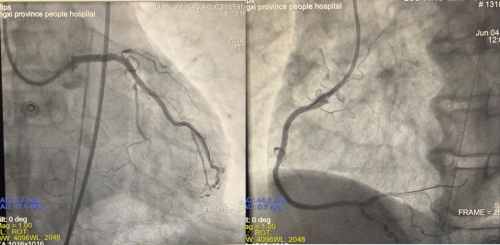

李林锋针对这种危重患者,带领科室小组成员展开积极的术前评估和讨论。患者确诊为极高危 NST-ACS患者,入院后当晚行冠脉造影检查评估,提示:左主干开口狭窄50%,末端狭窄80%,前降支开口后完全闭塞,血流TiMi0级,有同侧回旋支侧枝循环,但中远段血管显示不清,回旋支中段狭窄95%,血流TiMi3级,有至右冠侧枝循环,但侧枝仅显示左室后侧支,右冠分出锐缘支后完全闭塞,血流TiMi 0级。分析冠脉影像特点:左主干合并三支血管病变,其中两支为完全闭塞病变,且无残端,闭塞段长,开通难度大。仅存的回旋支管腔狭窄得仅剩一丝血流,斑块不稳定,介入手术极易发生慢血流/无复流现象。处理此类病变风险极大,犹如“达瓦孜”——新疆的一种走钢丝杂技,一步不慎,可能就是“万丈深渊”。

术前造影显示:左主干开口狭窄50%,末端狭窄80%,前降支开口后完全闭塞,回旋支中段狭窄95%,右冠分出锐缘支后完全闭塞